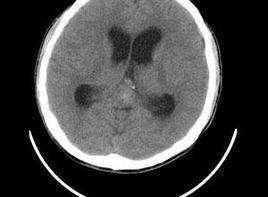

分析松果體區腫瘤的CT表現,診斷提供幫助。松果體區可見一類圓形軟組織腫塊,邊界清晰,密度均勻,其內可見點片狀鈣化影。頭顱CT掃描、核磁共振檢查可發現腫瘤並做定位診斷。